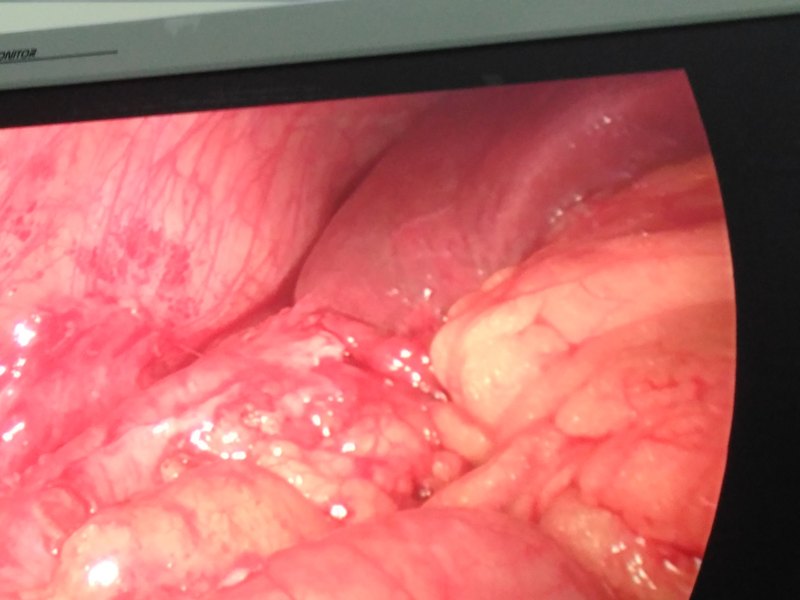

急性结肠憩室炎是一种常见疾病,结肠憩室好发于回盲部、升结肠和乙状结肠,也可分布全结肠,憩室可单发,多数为多发。临床上急性结肠憩室炎可在急诊抗炎补液后缓解,腹痛症状明显或伴有发热者需住院治疗,一般于禁食加强抗炎支持治疗后症状可缓解。大多数急性结肠憩室炎为急性蜂窝织炎,表现为结肠和系膜及其周围脂肪垂的炎症,病情进展可化脓坏疽穿孔,特别是憩室内伴有粪石,憩室根部较小者更易穿孔。结肠内容物有微小渗漏则有腹膜炎表现,大网膜多能覆盖病灶区,炎症局限,大多数保守治疗可免于急诊手术。当结肠憩室穿孔后就形成粪水性腹膜炎,需要及时急诊手术治疗,本病例部位在回盲部,CT复查回盲部憩室炎伴穿孔,阑尾已增粗考虑继发性阑尾炎,因此行腹腔镜下憩室切除+阑尾切除术,手术顺利。 总之,结肠穿孔破裂,排除肿瘤、异物刺伤和外伤,多数为急性结肠憩室炎所致。 结肠憩室炎只有大出血、穿孔、梗阻或脓肿形成等情况下,需急诊手术治疗。腹腔镜手术是其首选手术方式,对于憩室较大的可用内镜切割闭合器切除憩室,小憩室穿孔可直接套扎器套扎即可,也可全层倒刺线缝合。对于结肠炎症严重水肿明显,全层倒刺线缝合更安全,再将大网膜缝在边缘覆盖穿孔区,旁边放置引流,考虑肠漏可能大者放置冲洗引流双套管。